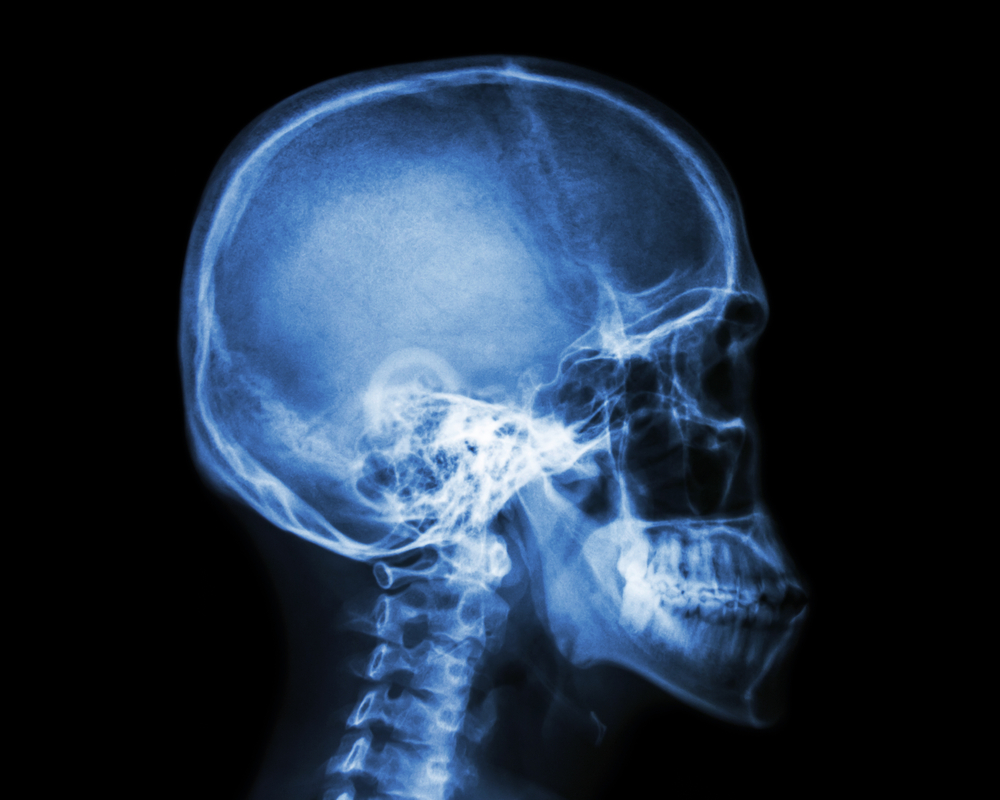

Kaukolės rentgeno tyrimas yra vaizdinimo priemonė, leidžianti medikams įvertinti kaukolės, veido kaulų, nosies ir antmakių kaulų būklę. Šis tyrimas nuo seno naudojamas kaip greitas ir nesudėtingas būdas įvertinti galvos sritį, kurioje yra ypatingai svarbus organas – smegenys.

Atlikus kaukolės rentgeno tyrimą, nuotraukos perduodamos radiologui ir gydytojui įvertinti. Ant nuotraukos aiškiai matomi tankesni audiniai, kaip kaulai – jie atvaizduojami šviesiai. Navikai, augliai ar kiti dariniai taip pat gali būti pastebimi kaip šviesesnės vietos. Nustačius pakitimus, prireikus gali būti skiriami papildomi tyrimai, pavyzdžiui, magnetinio rezonanso ar kompiuterinės tomografijos skenavimas.